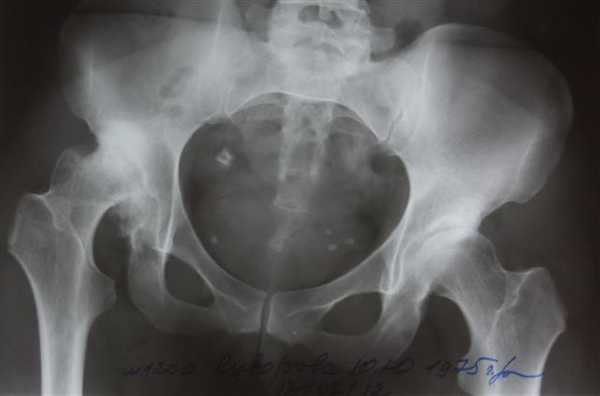

Перелом правой вертлужной впадины(на снимке слева).

Травма левого ТБС.